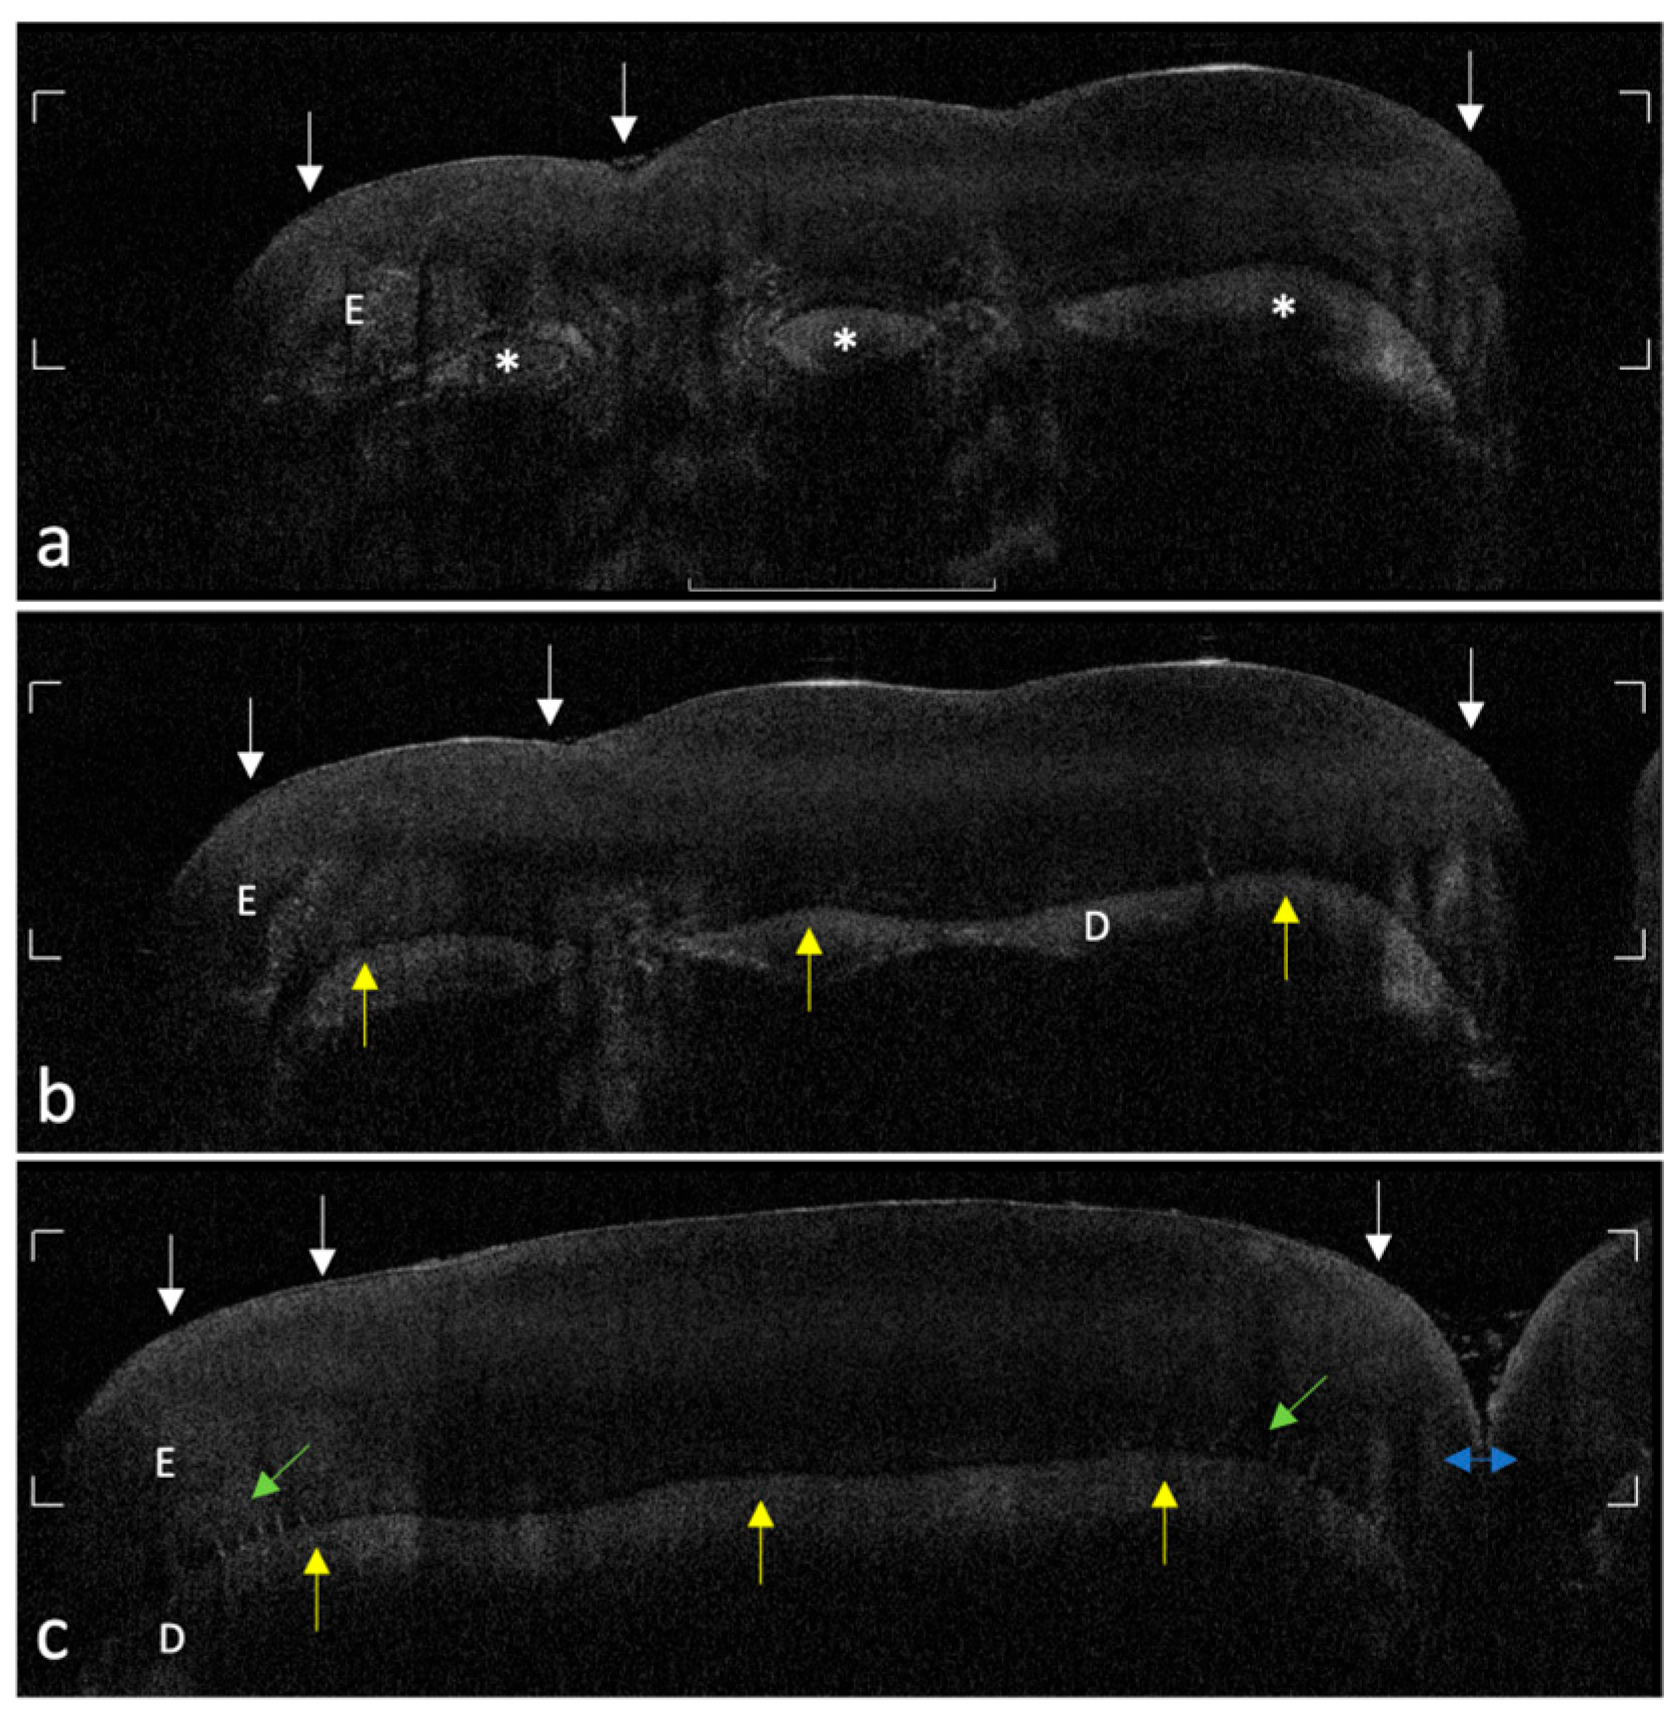

OCT imaging of healthy teeth exhibited consistent optical features distinctively reflecting anatomical and histological morphology in both FPM and incisors. In control teeth, OCT scans revealed a well-organized enamel and dentin layer with uniform optical properties, with a distinct superficial hyper-reflective interface at the enamel–air boundary. As expected in OCT imaging, the signal intensity gradually decreases with depth due to the intrinsic scattering properties of dental tissues. Within the enamel region, this depth-related attenuation appeared smooth and homogeneous, indicative of structurally intact and uniform mineral density throughout the enamel. The DEJ presented as a sharply demarcated, continuous hypo-reflective interface, clearly differentiating enamel from dentin. Internally, on the enamel side of the DEJ, minor anatomical features such as enamel tufts and spindles were observed as fine hyper-reflective projections arising perpendicularly from the DEJ into the enamel layer. Figure 1 illustrates an OCT scan of a healthy upper permanent molar, highlighting the superficial enamel–air interface, progressive enamel signal attenuation, and clearly defined DEJ.

Sequential OCT scans of a healthy upper permanent incisor are depicted in Figure 2 (panels a–c), progressing from the incisal margin toward the cervical central vestibular region. At the incisal edge (panel a), OCT identified three distinct, rounded dentin islands corresponding anatomically to mamelons characteristic of incisors. Progressing cervically (panels b and c), these dentin islands gradually merged into a continuous DEJ, demonstrating the natural anatomical transition in enamel and dentin stratification. This anatomical progression documented by OCT provides a critical baseline for interpreting pathological enamel alterations.

Figure 1. Representative OCT scan of the buccal surface of a healthy FPM. The superficial hyper-reflective enamel–air interface represents the intact enamel surface (white arrows). The DEJ is clearly delineated as a continuous hypo-reflective boundary (yellow arrows) between enamel (E) and dentin (D). Fine internal hyper-reflective projections (green arrows) depict normal anatomical structures corresponding to enamel tufts and spindles arising perpendicularly from the DEJ.

Figure 2. Sequential OCT scans (ac) of a healthy upper permanent incisor, acquired from the incisal edge progressing cervically toward the central vestibular region. (a) Three distinct rounded islands of dentin (asterisks), anatomically corresponding to mamelons at the incisal margin (b,c), show the progressive anatomical merging of these dentin islands into a continuous dentino–enamel junction (DEJ, yellow arrows), between a continuous layer of enamel (E) and dentin (D). In panel (c), enamel tufts (green arrows) are visualized as fine hyper-reflective projections arising from the enamel side of the DEJ. The adjacent incisor is partially visible within the interproximal space (blue double-headed arrow), confirming spatial resolution and lateral tissue continuity. Across all panels, the superficial enamel–air interface (white arrows) appears as a continuous hyper-reflective band, indicating surface integrity.